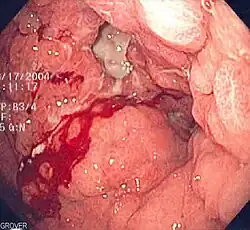

| Endoscopic image of linitis plastica, where the entire stomach is invaded with stomach cancer, leading to a leather bottle like appearance | |

Linitis plastica (sometimes referred to as leather bottle stomach) is a morphological variant of diffuse stomach cancer in which the stomach wall becomes thick and rigid.[1]